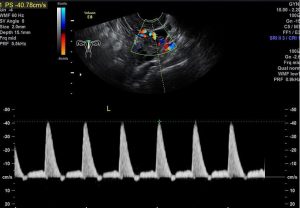

子宫是孕育生命的摇篮,子宫动脉及其分支为它提供源料,输送营养,为胚胎发育做好准备。怀孕后,子宫动脉将富含营养物质的母血送至胎盘绒毛间隙,与胎儿血液进行物质交换。子宫内膜如同种子发育的土壤,子宫动脉及其分支为摇篮和土壤提供源源不断的血供和营养,保证胚胎发育所需要的各种养分。

简单理解就是:子宫动脉是为胎儿输送成长液的轨道。如果因各种原因导致子宫动脉血供异常,阻力过大,血液灌流不足,营养供给跟不上,就会影响胚胎的着床、发芽及生长,从而引起流产。

一项基于1700多例复发性流产患者进行的回顾性分析显示复发性流产有明确原因的达63%,排除胚胎因素后,自身免疫和血栓前状态导致反复流产者所占比例最大。而孕期的血栓状态最直接的影响就是子宫动脉血流,因此不少反复自然流产的患者伴有子宫动脉血流的异常。